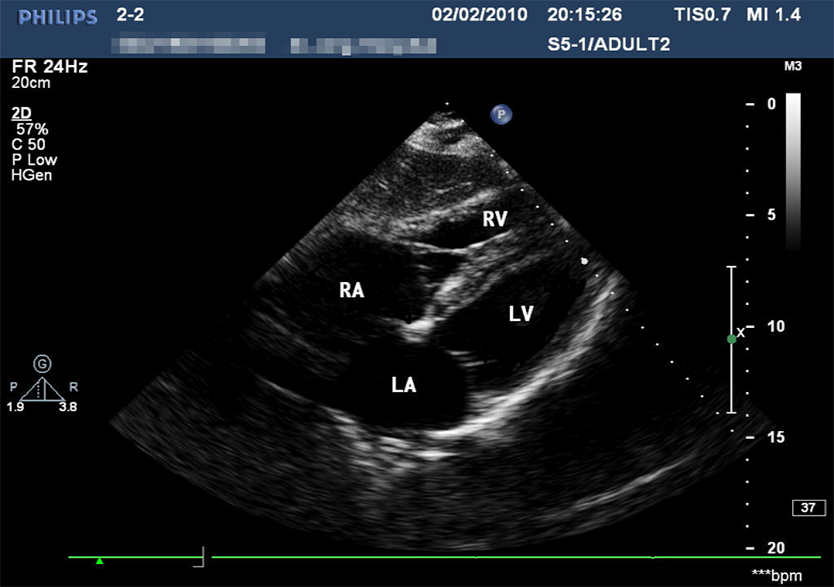

创伤超声重点评估平台2.0

产品型号 NO.TY4084

产品尺寸(mm) 987×444×269